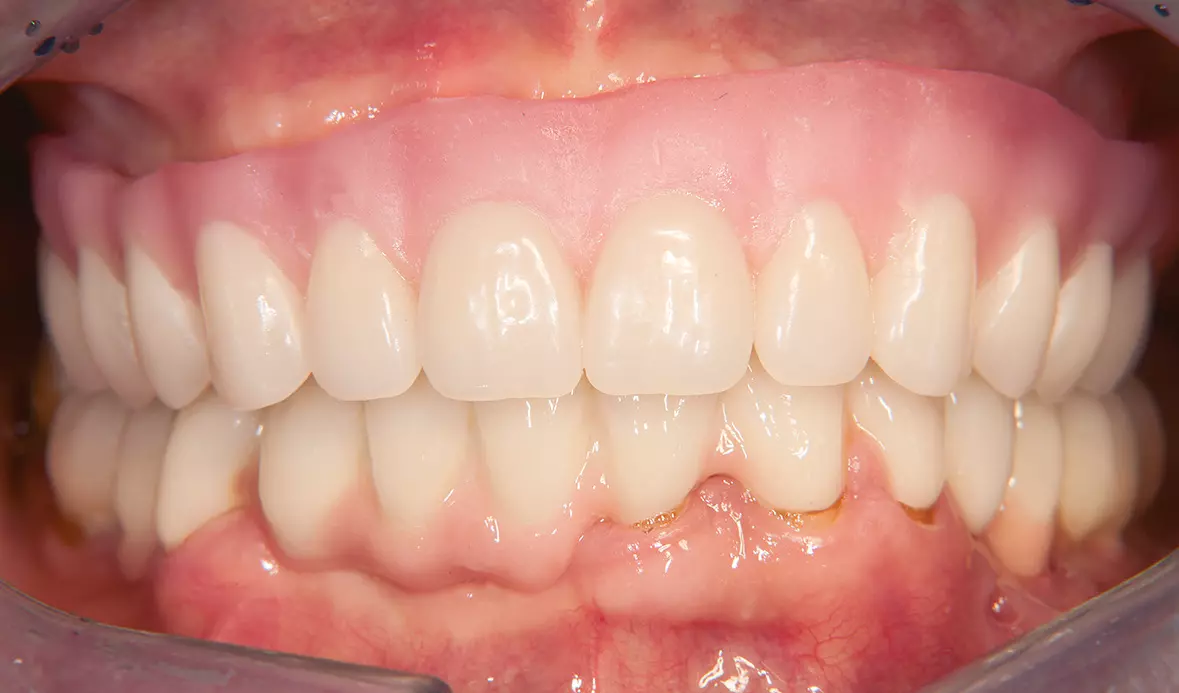

Abb. 44: Fertige Prothese im Mund. Dr. Michael Leistner

Abb. 44: Fertige Prothese im Mund.

Abb. 45: Laterale Ansicht. Dr. Michael Leistner

Abb. 45: Laterale Ansicht.

Abb. 48: Lippenbild. Dr. Michael Leistner

Abb. 48: Lippenbild.

Abb. 50: Ein natürliches Lachen. Dr. Michael Leistner

Abb. 50: Ein natürliches Lachen.